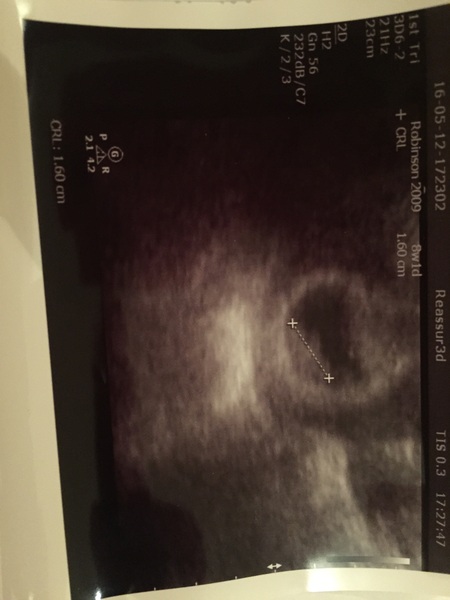

Checking back in after a quiet week or so...

Had booking in appointment yesterday and a private early scan. Did make things feel more real, but still can't quite get my head around that little blob being inside me!! Scan put me back by 1 day so will see what the 12w one says! Edging even closer to Xmas and I'm just about allowing myself to believe it and start planning!